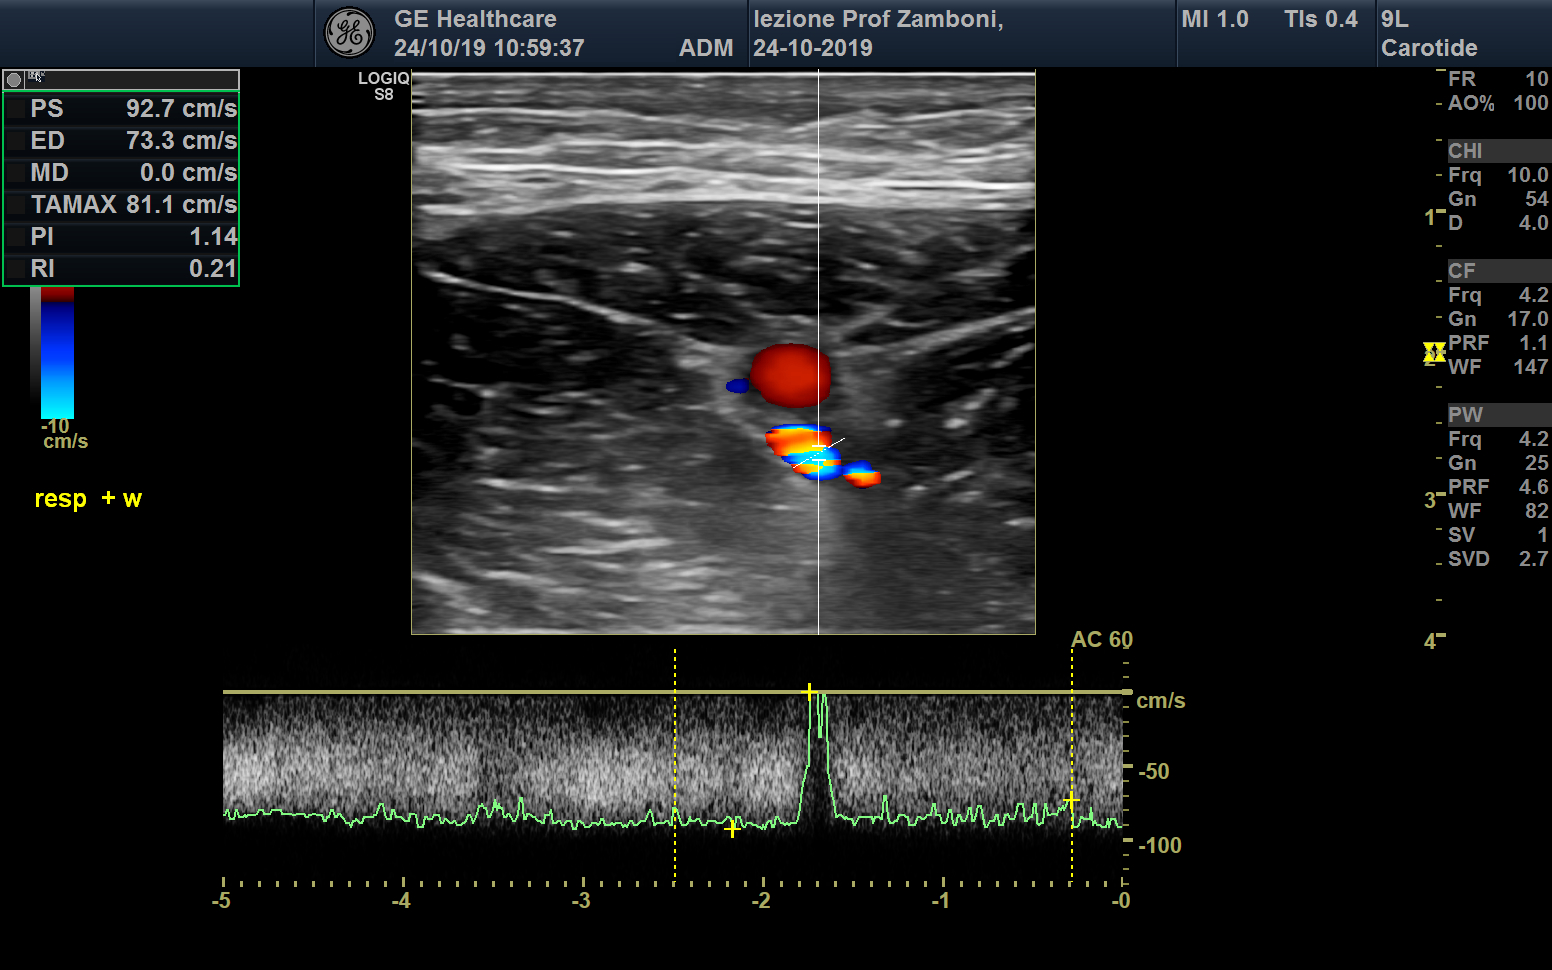

PW V. Femorale respiro e wunstorf

JPEG image icon PW V. Femorale respiro e wunstorf.jpg — JPEG image, 666 kB (682276 bytes)